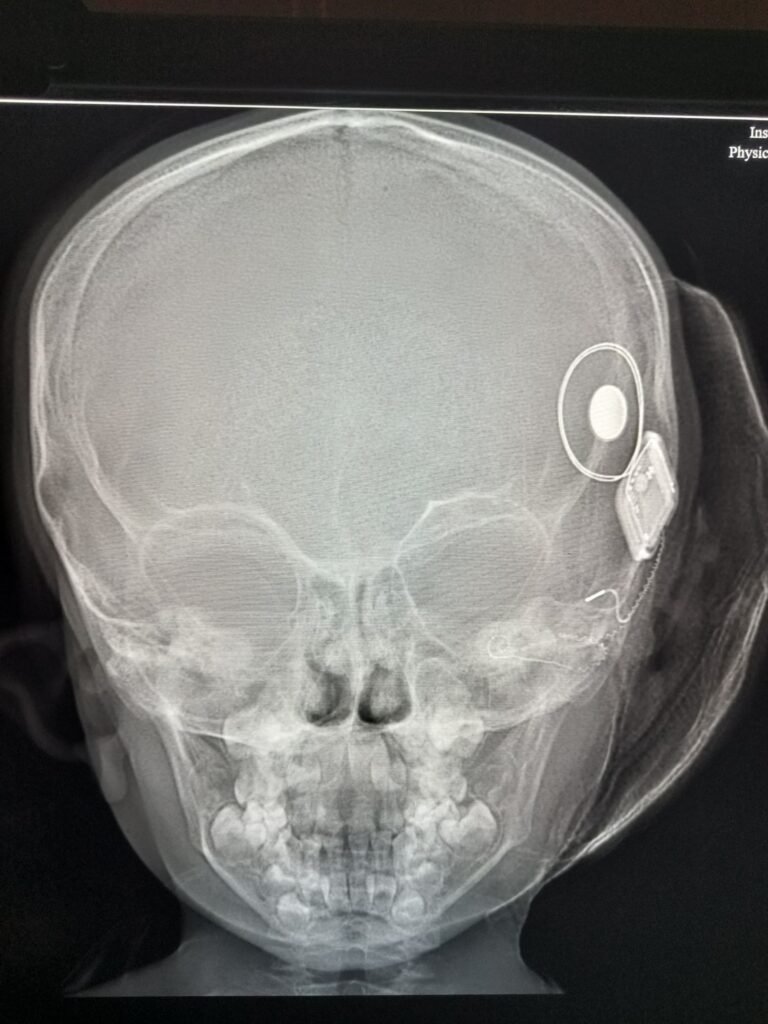

*नवी मुंबईतील ४ वर्षांच्या रोहित खन्नाला (नाव बदलले आहे) त्याचे पालक मेडिकव्हर हॉस्पिटलमध्ये उपचारांसाठी घेऊन आले होते.* त्याला ऐकू येत नसल्याची आणि त्याच्या वयाच्या इतर मुलांप्रमाणे तो बोलू शकत नसल्याची चिंता त्याच्या पालकांना सतावत होती. BERA सह एक सखोल तपासणी करण्यात आले, ज्यातून दोन्ही कानांमध्ये तीव्र श्रवणदोष असल्याचे निदान झाले. याचा अर्थ, ते मूल बोलण्याच्या विकासासाठी आवश्यक असलेले आवाजच ऐकू शकत नव्हते. दोन वर्षांपूर्वी म्हणजेच वयाच्या दुसऱ्या वर्षी, त्या मुलाला पहिल्यांदा दोन्ही कानांमध्ये तीव्र श्रवणदोष असल्याचे निदान झाले होते. रुग्णाच्या कुटुंबाला उपचारांच्या पर्यायांविषयी समुपदेशन करण्यात आले. कुटुंबासाठी, हे निदान भावनिक आणि आर्थिकदृष्ट्या अत्यंत त्रासदायक होते. कॉक्लियर इम्प्लांटेशन, तीव्र श्रवणदोष असलेल्या मुलांसाठी सर्वात प्रभावी उपचार, ही एक खर्चिक प्रक्रिया आहे ज्यासाठी त्याच्या पालकांना आर्थिक अडचणींचा सामना करावा लागत होता. हॉस्पिटल टीमच्या पाठिंब्याने आणि मार्गदर्शनाने, ‘द हान्स फाउंडेशन’च्या मदतीने ते कुटुंब या साऱ्या आव्हानांवर मात करू शकले, ज्यामुळे या चिमुकल्याचा नव्या आयुष्याचा प्रवास सुरु झाला. त्यानंतर हॉस्पिटलमध्ये या बालरुग्णावर उजव्या बाजूच्या कॉक्लियर इम्प्लांटची शस्त्रक्रिया करण्यात आली. ही प्रक्रिया यशस्वीरित्या पार पडली, ज्यामुळे मुलाला श्रवण क्षमता परत मिळाली. येत्या काही महिन्यांत या रुग्णाला नियमित श्रवण प्रशिक्षण आणि स्पीच थेरपीची दिसी जाईल. आता त्या बालरुग्णाला पहिल्यांदाच ऐकण्याची, बोलण्याची, भाषा शिकण्याची आणि विविध आवाजांचा अनुभव घेण्याची संधी मिळाली आहे, ज्यामुळे संवाद, शिक्षण आणि उज्ज्वल भविष्याचे मार्ग खुले झाले आहेत. नव्याने सुरू झालेल्या या क्लिनिकचा उद्देश हा आहे की, अशा अधिकाधिक मुलांना वेळीच निदान, योग्य उपचार आणि उत्तम जीवनमान जगण्याची संधी मिळावी.